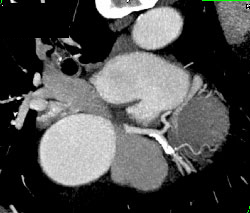

Aortic Valve Replacement (AVR)- See Video File for Nice 4D